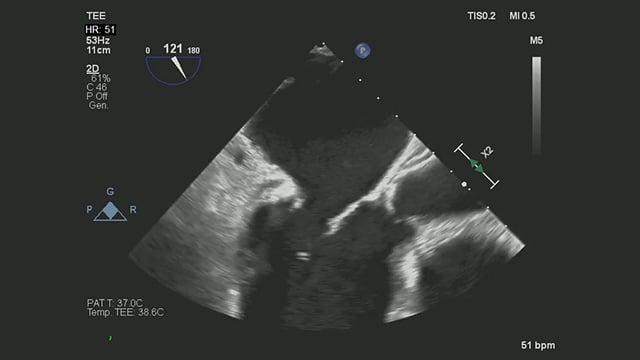

Severe MR in a high-risk patient with a suboptimal anatomy for M-TEER: what other options can we find?

Multimodality imaging reveals fibro-calcific leaflet disease, restricted motion, and a short posterior leaflet, making him a suboptimal candidate for M-TEER and prompting consideration of transcatheter mitral valve replacement. How would you treat?